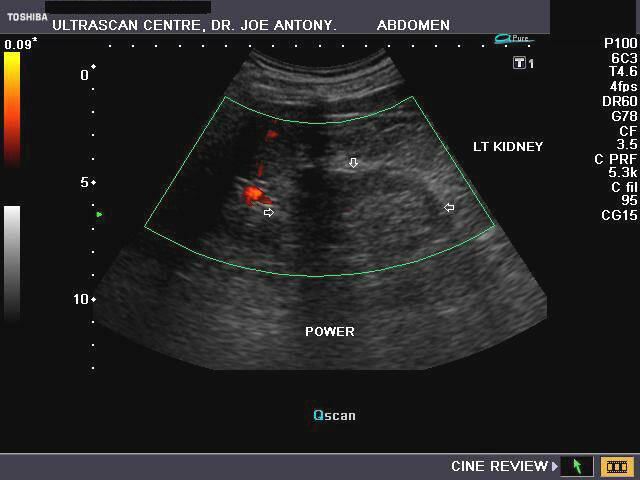

The left kidney in this male child shows a prominent column of renal cortex in the middle third of the kidney. This column of tissue is seen encroaching on the renal sinus, with the renal contour (outer margins of the left kidney) appearing normal. Color Doppler images of the left kidney show normal vascular pattern in the column. The echogenicity and echotexture of the column of tissue appears similar to the adjacent renal cortex. These ultrasound images and the sonographic findings are typical of what is called hypertrophied column of Bertin. The current terminology for this benign normal variant is junctional parenchyma. This new term for a long understood normal variant, is used as the renal tissue in the column of Bertin does not show any evidence of hypertrophy. The tissue in the junctional parenchyma/ hypertrophied column of Bertin is absolutely normal renal parenchyma and contains renal cortex, pyramids and septa or columns of Bertin. the renal tissue in the column is continuous and merges with the adjacent cortical tissue of the kidney. The column of Bertin is most commonly seen involving the left kidney as in the case above.